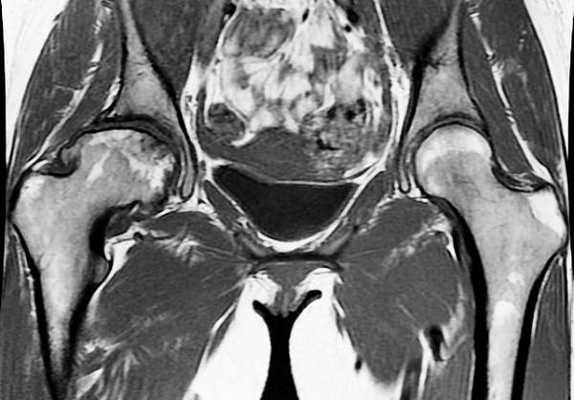

Артрит правого тазобедренного сустава на снимке МРТ